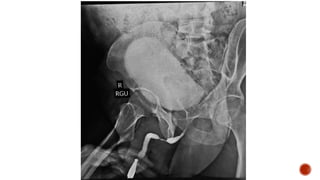

 Indication

 Contrast

 Technique

 Parts of male urethra

 Trazograf (Ditrazoate sodium 76%)

 Ionic water soluble iodinated contrast

 Dilution :

 1:2 for RGU

 1:10 for MCU

 Anterior :

 penile

 bulbar

 Posterior :

 membranous

 prostatic

 Verumontanem

 Bulbomembranous junction at the level of the inferior margin of the obturator

foramen